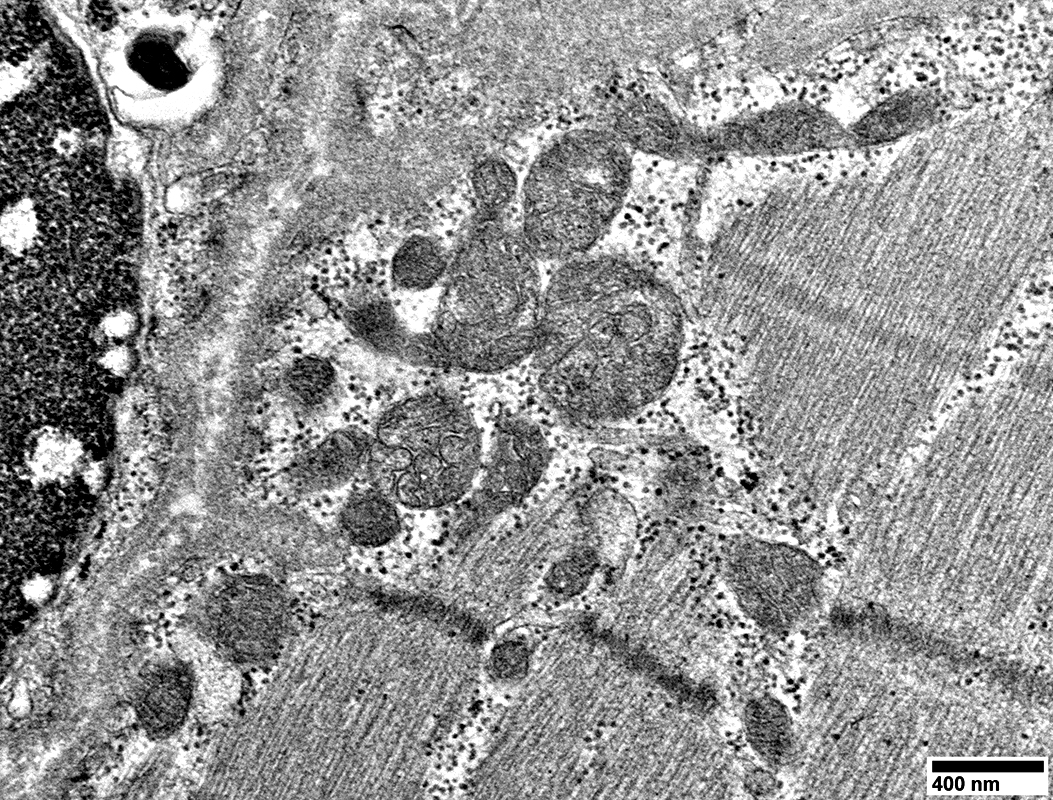

MELAS: Capillaries

From: R Schmidt

Endomysial capillaries

Endothelial cells with many vesicles

Large size

Thick wall